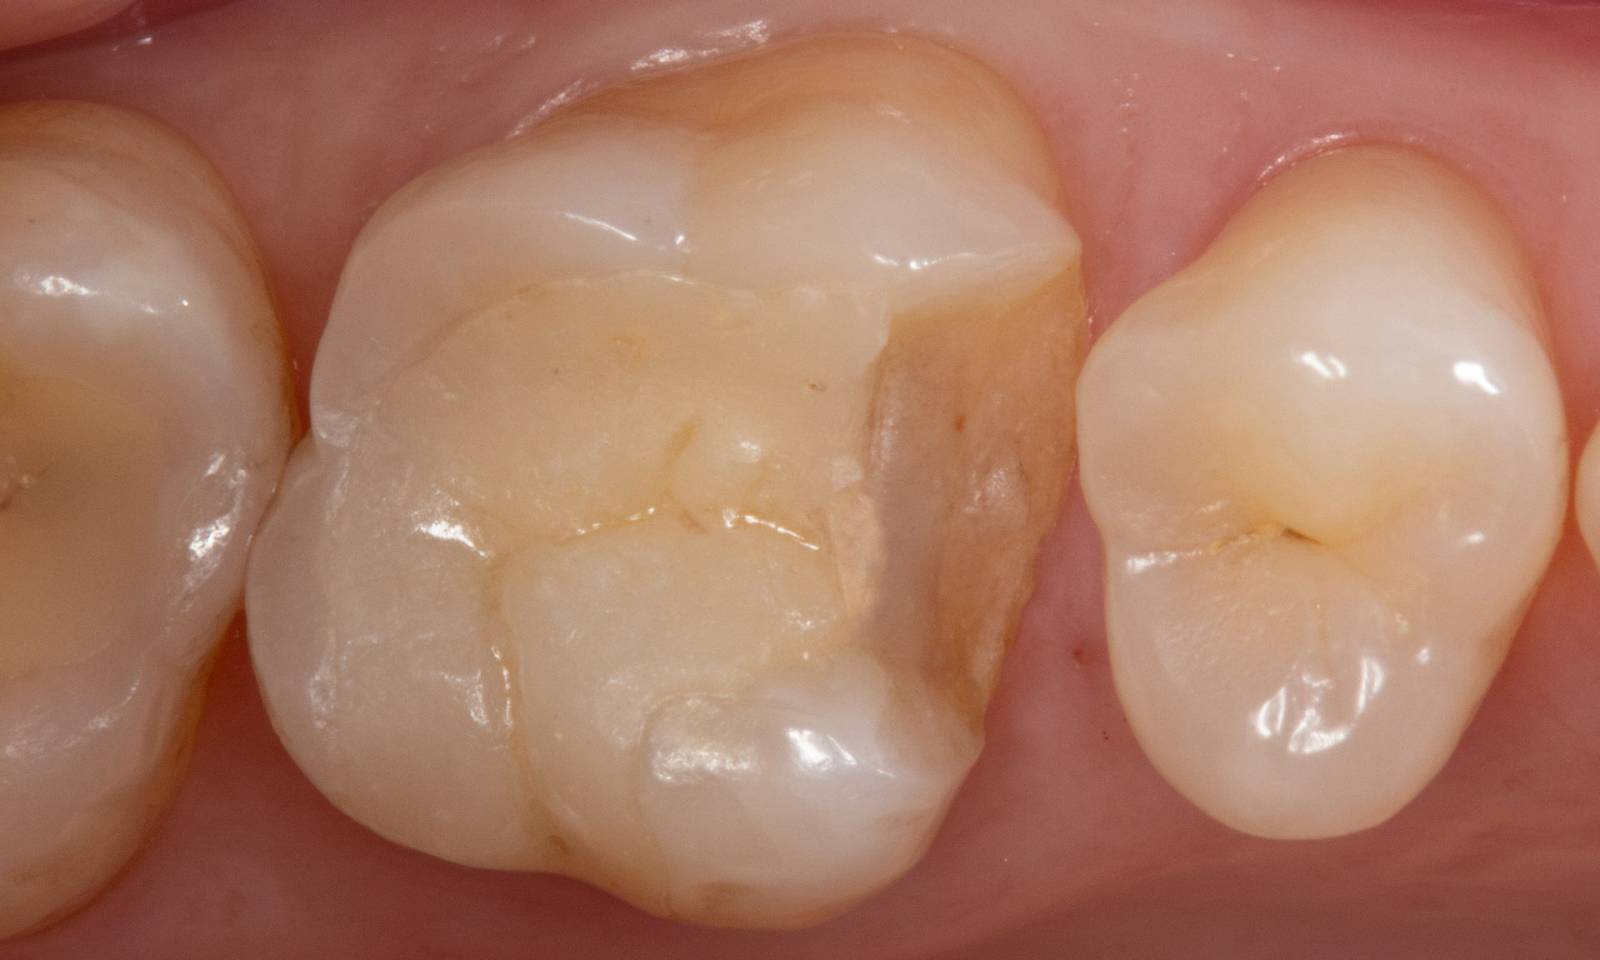

Composite filling, tooth 16, before CEREC treatment

Before

Large insufficiency of the composite filling on tooth 16 with distal marginal ridge cracks, a lingual wall crack and distal recurrent decay.